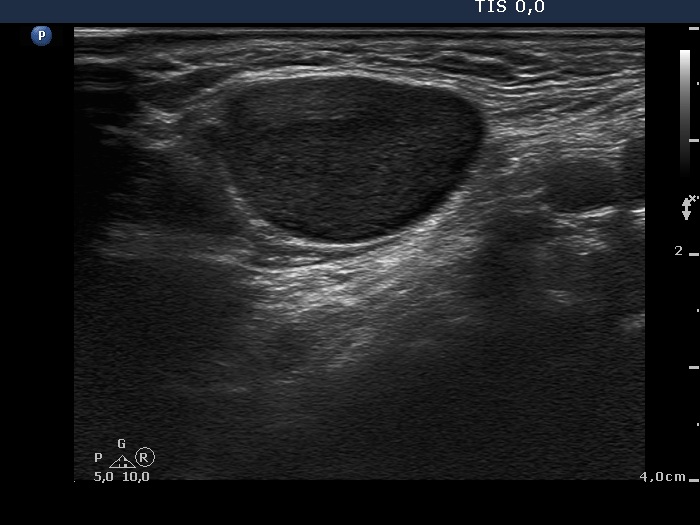

Lymph nodes in the neck - Case 6. (ultrasonographic picture 4)

Metastasis of an adenocarcinoma of the colon

Right submandibular area, horizontal scan. There is a large lymph node without regular hilum.